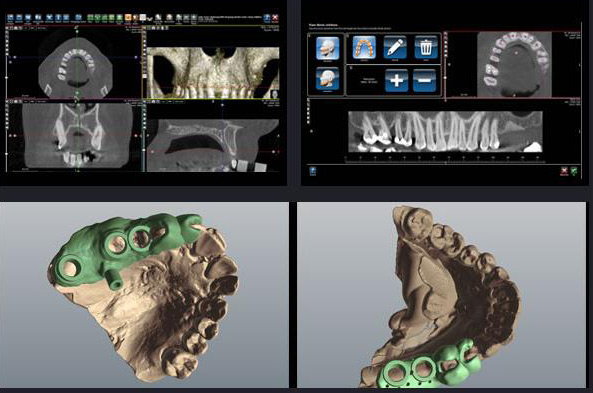

数字化种植牙取代了传统种植牙手术需要切开牙龈翻瓣→打孔种入种植体→缝合伤口等复杂流程,通过数字化工具获得患者口腔数据,重建口腔模型进行数字化模拟种植过程,根据患者牙槽骨密度、角度、高度、宽度,精密避开血管和神经,再按照患者咬合习惯,自然牙齿排列位置制作全程种植导板,进行微创精密种植手术。胡主任表示,种植牙全程采用数字化技术,精准扫描口腔信息,获取口腔各项数据,全数字化智能模拟种牙,手术前、中、后所有步骤提前模拟,确保人工牙根可以牢固地跟骨组织精密连接在一起,精密操作,种牙手术创伤微小、术后无肿胀、疼痛、感染等并发症的发生风险。

数字化种植牙取代了传统种植牙手术需要切开牙龈翻瓣→打孔种入种植体→缝合伤口等复杂流程,通过数字化工具获得患者口腔数据,重建口腔模型进行数字化模拟种植过程,根据患者牙槽骨密度、角度、高度、宽度,精密避开血管和神经,再按照患者咬合习惯,自然牙齿排列位置制作全程种植导板,进行微创精密种植手术。胡主任表示,种植牙全程采用数字化技术,精准扫描口腔信息,获取口腔各项数据,全数字化智能模拟种牙,手术前、中、后所有步骤提前模拟,确保人工牙根可以牢固地跟骨组织精密连接在一起,精密操作,种牙手术创伤微小、术后无肿胀、疼痛、感染等并发症的发生风险。